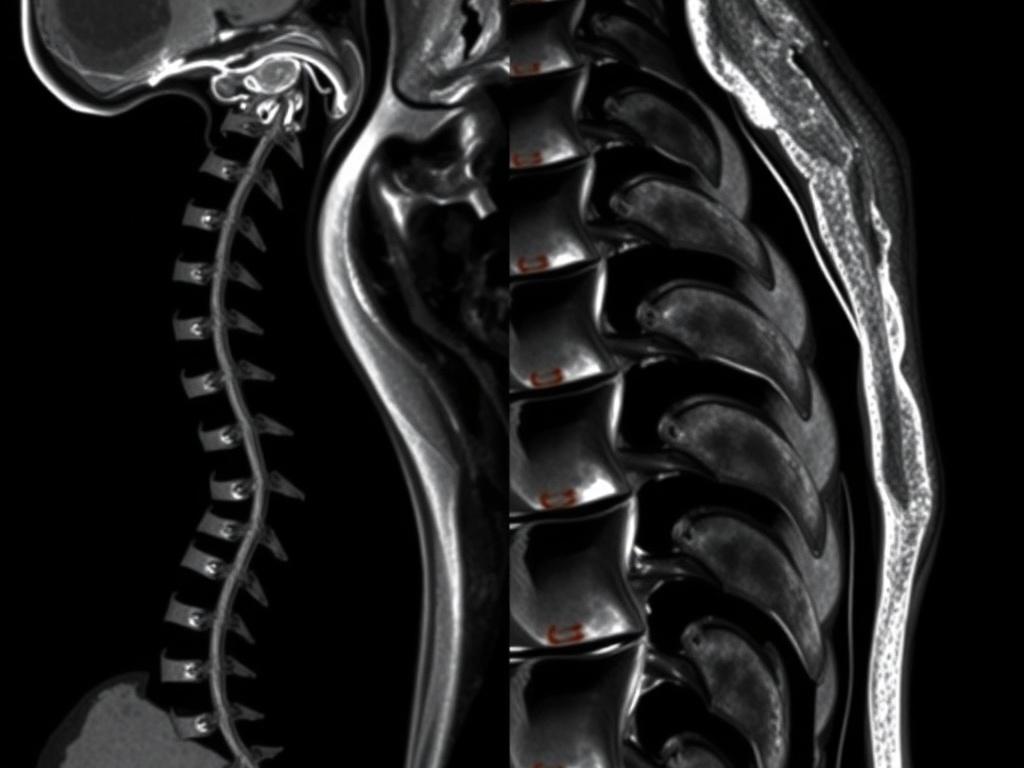

Магнитно-резонансная томография (МРТ) грудного отдела позвоночника – это высокотехнологичный метод диагностики, который позволяет получить полный объем информации о состоянии тканей и структур в данной области. Процедура используется для выявления различных заболеваний и состояний, включая опухоли, воспалительные процессы, травмы и заболевания межпозвоночных дисков. Проводится процедура с контрастом, что улучшает визуализацию и помогает детально рассмотреть состояние органов и тканей грудной клетки.

Процедура магнитно-резонансной томографии проходит в комфортной и безопасной обстановке. Пациент располагается на столе аппарата, который затем постепенно задвигается в магнитное поле. Важно оставаться неподвижным, чтобы получить четкие снимки. В процессе обследования вы будете слышать звуки, создаваемые аппаратом, что абсолютно нормально. Если назначено МРТ грудной клетки с контрастом, контраст вводится intravenously перед началом исследования, чтобы улучшить видимость некоторых тканей и органов.

- высокое качество изображения – позволяет увидеть мельчайшие изменения в тканях;